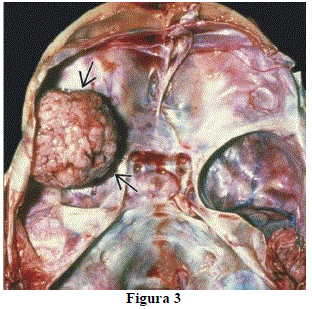

Analise a imagem da figura 3:

Sobre ela, assinale a alternativa INCORRETA.